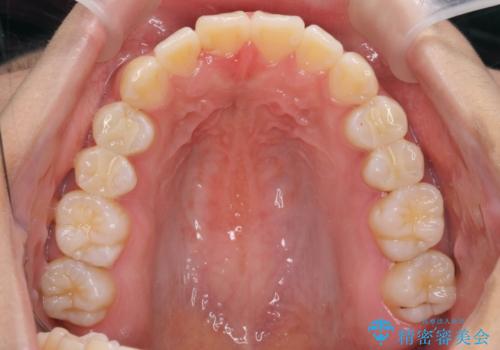

- 前歯の目立つねじれを矯正治療で治したい、と来院されました。

マウスピース矯正を始める前に、ねじれを取るのが短期間で済む部分ワイヤー小矯正を行うことで、全体的な治療期間を短くする治療計画を実行していきます。

前歯のねじれはマウスピース矯正の苦手な動きになり、治療期間が長くなる原因になりやすいです。